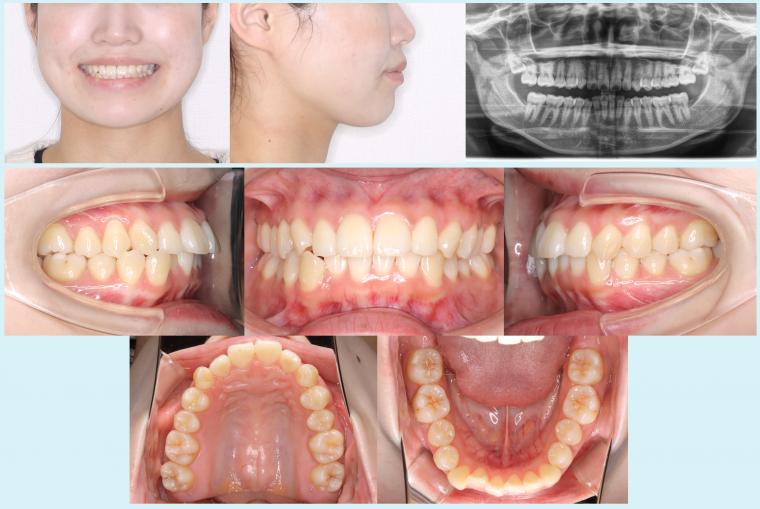

2025.09.28 #45 軽度叢生を治療した症例 「下の歯のデコボコ」が気になると来院された患者さんです。右下の犬歯が歯列の外側に出ていて、部分的に反対咬合になっている咬み合わせでした。上の歯並びは左右の犬歯が斜めになっている状態でしたが、ご本人は気... 症例集(マウスピース矯正)

2024.07.17 #29 金属アレルギーのためマウスピースを使用した症例 治療前治療中治療後「歯ならびが気になる」と来院された患者さんです。右の前歯が一部、反対咬合になっている咬み合わせで、金属アレルギーがあるとのことでした。治療前に皮膚科を受診していただき、パッチテストか... 症例集(マウスピース矯正)

2024.05.22 #26 10か月ですきっ歯を治療した症例 治療前治療中治療後「前歯が出ている。前歯の間が開いているのを治したい。」とのことで来院された患者さんです。診断を行った際にはまだ骨格の成長があると考えられたため、治療開始までに6か月待っていただいてか... 症例集(マウスピース矯正)

2023.12.05 #15 マウスピースで咬み合わせを治療した症例 受け口を気にされて、来院された患者さんです。右の前歯が反対咬合になっている咬み合わせでした。上下の骨格のバランスはほとんど問題無かったため、外科的手術を併用しない方針となりました。最初に右側の親知らず... 症例集(マウスピース矯正)